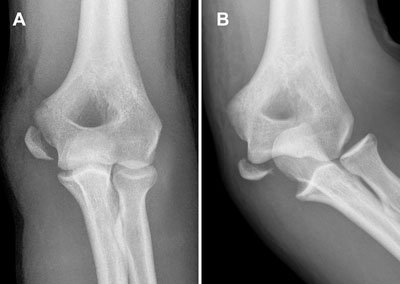

پارگی عضلات سینه معمولا در پرس سینه با هالتر[۶] دیده می شود. ضایعه در عضله دوسر معمولا در سربلند آن دیده می شود درد آن در جلوی بازو احساس می شود. درد در ناحیه فرق لقمه ای استخوان بازو که محل چسبندگی تمام تاندونهای بازکننده ساعد است پدیده ای بسیار شایع بوده و از آنجایی که در ورزش تنیس بیشتر دیده می شود. به اختصار بازوی تنیس باز لقب گرفته است. علت به وجود آمدن چنین حالتی استفاده غلط از راکت و تکنیک نادرست است. قرینه چنین التهابی در اپی کندیل[۷] داخلی جایی که تاندون عضلات خم کننده ساعد می چسبد بازوی گلف باز نامیده می شود.